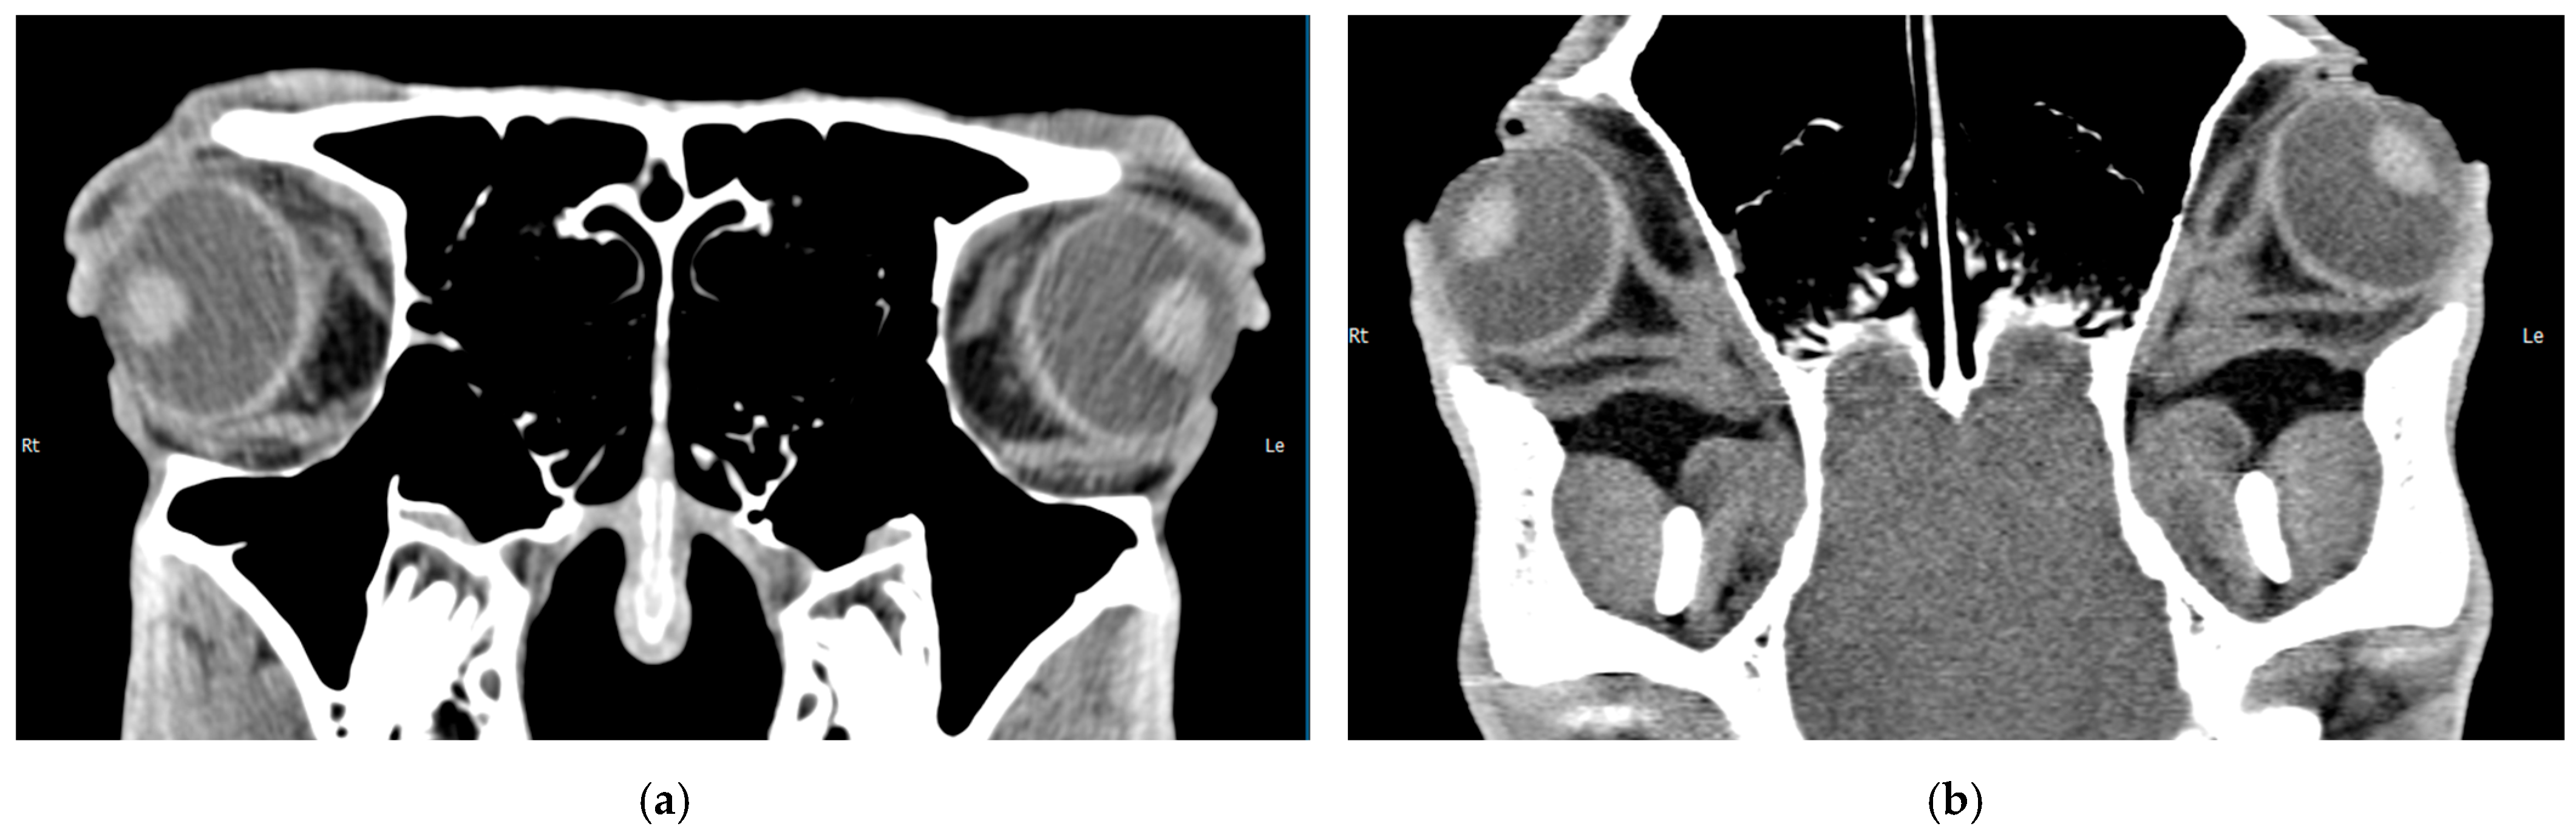

3.2.2. Sectional Imaging